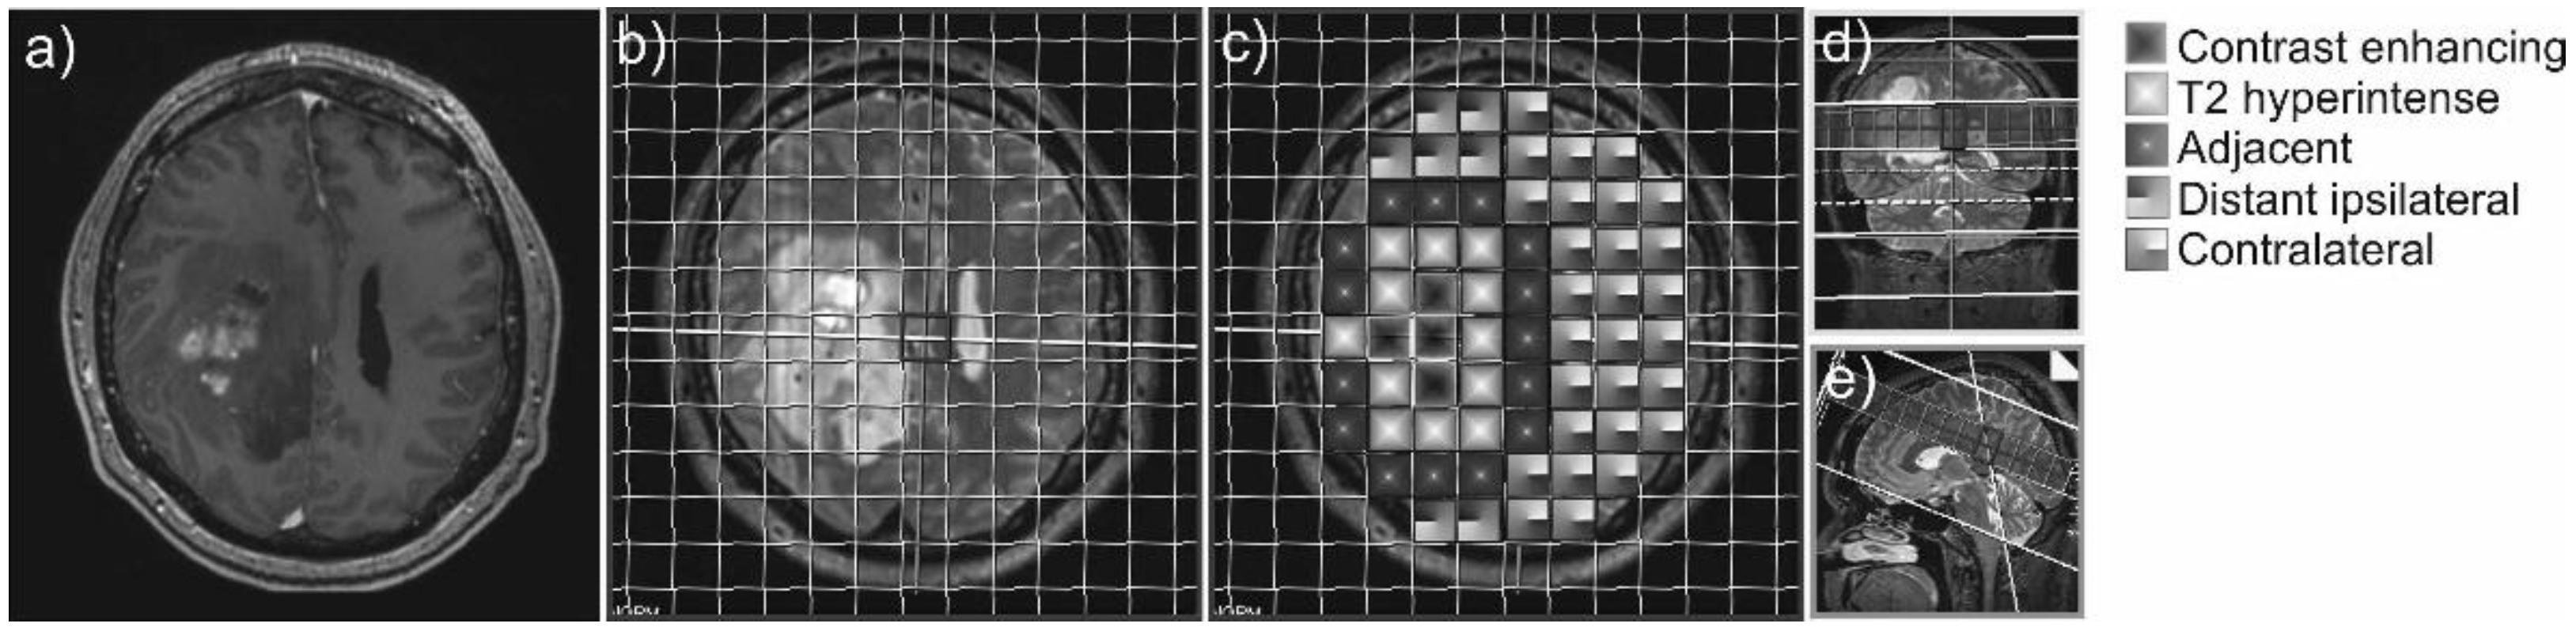

2.3. Data Processing and Analysis